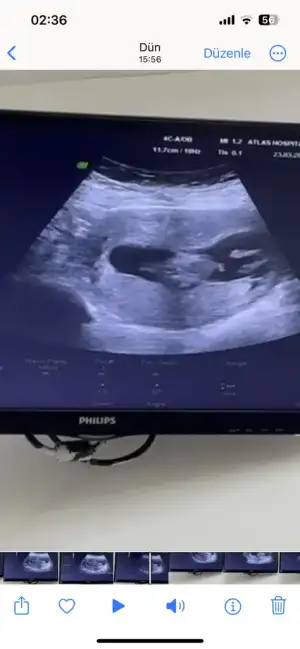

Banada yorum yaparmisiniz acaba ilk foto 13+6 Ken olan ulturoson resmi ikincide 6+7 haftalık ulturoson resmi şuan ,16 haftaligiz fktotumuz hala cinsiyet söylemedi

• Snapchat-1597038519.webp

Snapchat-1597038519.webp

19,2 KB · Görüntüleme: 79

• IMG_20240209_204320.webp

IMG_20240209_204320.webp

19,4 KB · Görüntüleme: 80